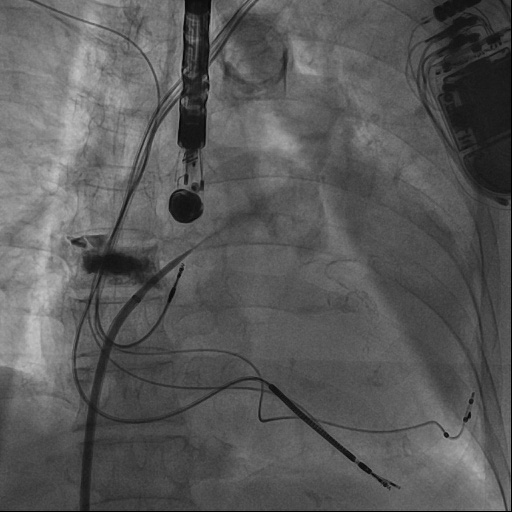

心血管内科团队与超声诊断科、麻醉科进行了术前会诊,对钟婆婆病例进行研讨分析,制定了周密手术方案及并发症应急预案。术中唐波副主任医师与沈松林主治医师通力合作,经右侧股静脉,在食道超声引导下穿刺房间隔,将长鞘顺利进入患者左心耳,利用猪尾导管进行造影,同时进行测量,选择合适的封堵器封堵左心耳。术中,超声诊断科为钟婆婆实时进行经胸、经食道超声心动图检查,以实时精密的测量为手术医师提供有效可靠地帮助;麻醉团队为钟婆婆诱导麻醉、气管插管、全麻和机械通气及全程监测,各学科通力配合,顺利完成手术。

图1、在食道超声指导下进行房间隔穿刺。